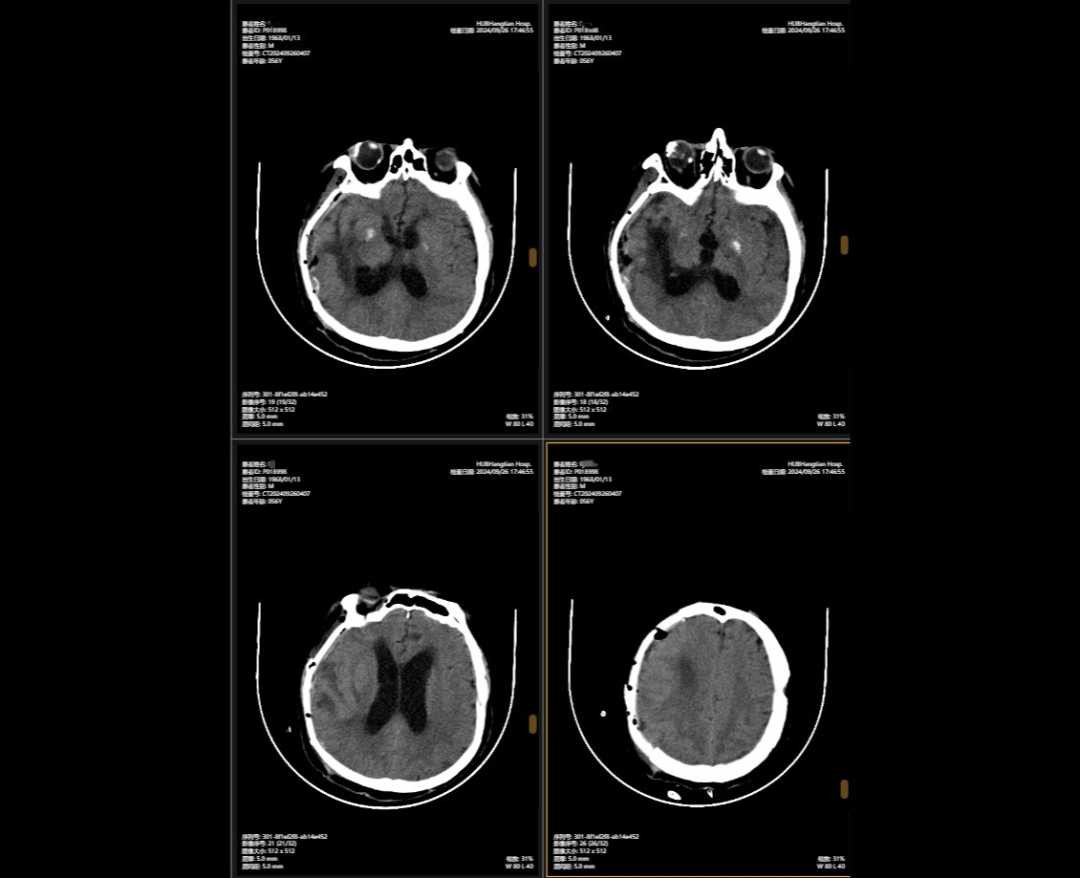

顱骨缺損修補(bǔ)術(shù)前術(shù)后對(duì)比

李先生的病情穩(wěn)定后,神外團(tuán)隊(duì)緊繃了數(shù)周的神經(jīng)終于得以松弛,他們隨即為他制定了顱骨缺損與腦積水治療方案,2024年9月,李先生接受了顱骨缺損修補(bǔ)術(shù),“修補(bǔ)”之前取下的頭骨,保護(hù)大腦,解決顱內(nèi)壓力不穩(wěn)問題,術(shù)后他的神經(jīng)紊亂癥狀明顯改善;三個(gè)月后,神外團(tuán)隊(duì)繼續(xù)施行腦室-腹腔分流術(shù),通過植入的分流管,解決了腦積水問題,讓腦壓恢復(fù)正常。